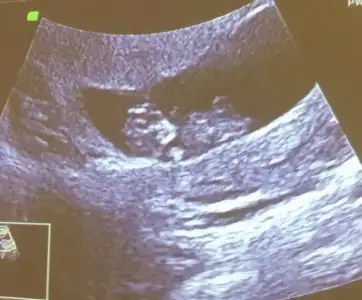

Net göremedim nubu yani dikte degil paralelde kafa sekli erkek bazen kafa yanıltıyor başka usg varsa tahmin ederim

Bu usg kaç hafta burdada nubu ne dik nede paralel yani pozisyonla alakalı oluyor böyle usgler beni yanıtabiliyor ama hemen kafa şeklini yazarımMerhaba haber vermek istedim baba kız bunu demiştiniz ama tutmadı ikinci oğlum geliyor sağlık olsun![]()